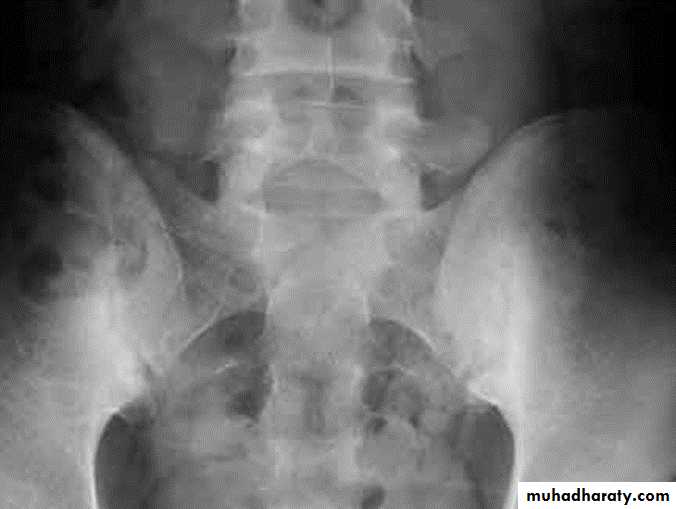

DEVELOPMENTAL DYSFLASIA OF HIP (CONGENITAL DISLOCATION OF THE HIP)

An abnormally lax joint capsule allows the femoral head to fall out of the acetabulum, leading to deformation.

CDH occurs most commonly (70%) in the left hip. Bilateral involvement is seen in 5%.

Radiographic features:

6 months and later

* AP veiw ( femural epiphysis are visualized ):* Superolateral displacement of proximal femur (disturbed shenton’s line )

* Increase in acetabular angle

* Small capital femoral epiphysis

Femoral head is located lateral to Perkin's line

Abnormal sclerosis of the acetabulum

Shallow acetabulum